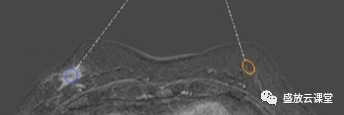

影像学表现

征象分析

特点归纳

诊断结果